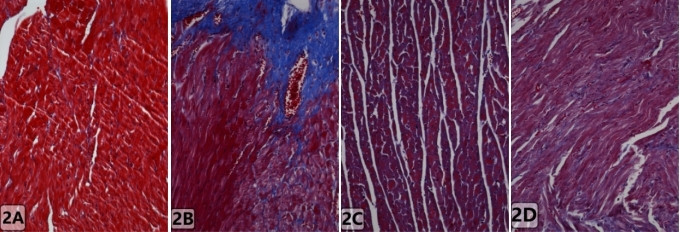

2 结果 2.1 各组大鼠心肌组织病理学变化光镜下Shame组心肌组织形态学正常,心肌纤维结构排列紧密,无明显充血、水肿及渗出等。CLP组可见心肌细胞明显水肿,呈带状空泡样变形,间质血管扩张充血严重,心机纤维排列紊乱,炎性细胞浸润明显(图 1)。CLP+ES组和CLP+TAK-242组与CLP组相比,心肌细胞水肿及坏死较减轻,间质仍有少量的炎性细胞浸润,心肌纤维排列较规整,但不及Shame组;TLR4、MyD88、NF-κB蛋白在脓毒症心肌组织中阳性表达呈棕褐色(图 2),于Shame组少量弱阳性表达,于CLP+ES组及CLP+TAK-242组中阳性表达明显减轻;正常组大鼠心肌组织肌纤维表达明显,无纤维化,发生脓毒症后胶原纤维表达增强,纤维化严重(图 3),给予β受体阻滞剂(艾司洛尔)和TLR4抑制剂后,纤维化组织较脓毒症组减少。说明发生脓毒症时,引起大鼠心肌组织的损伤,而β受体阻滞剂(艾司洛尔)与TLR4抑制剂会减轻脓毒症导致的心肌细胞损伤。

| Sham:假手术,CLP:盲肠结扎穿孔术,CLP+ES:盲肠结扎穿孔术后给予艾司洛尔,CLP+TAK-242:盲肠结扎穿孔术后给予TLR4抑制剂;棕褐色:TLR4、MyD88、NF-κ B阳性表达。免疫 组织化学染色 中倍放大 图 2 各组大鼠心肌组织中TLR4、MyD88及NF-κ B的表达变化 Fig 2 Expression of TLR4, MyD88 and NF-κ B in myocardial tissue of rats in each group |